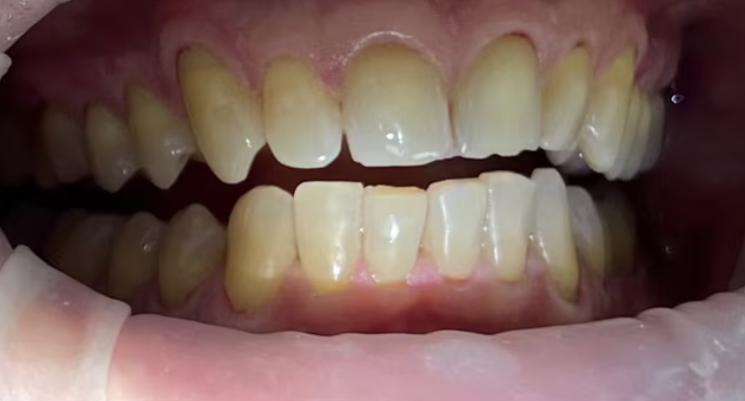

На странице представлено портфолио стоматологий Москвы с работами до и после профессиональной чистки зубов. В нашем портфолио собраны разные клинические случаи: от удаления незначительного налета до снятия массивного поддесневого камня. Здесь вы можете увидеть, как возвращается естественный цвет и внешний вид зубов после процедуры. Изучите результаты до и после чистки зубов, чтобы увидеть реальный эффект и выбрать клинику в Москве, где профессиональная гигиена поможет вернуть зубам здоровый вид.

Профгигиена

Пациентка регулярно приходит за профессиональной гигиеной зубов и полости рта

Доктор: Карапетян Фреда Сергеевна